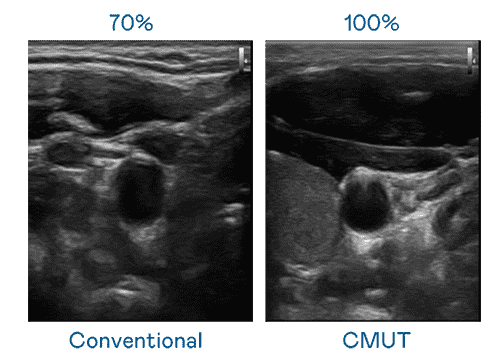

CMUT 技术是一种用电容式微机电元件来产生超音波讯号的技术。。。。与传统 PZT 压电式技术相比,,,CMUT 频宽增加 30%,,更宽频的超音波讯号让影像解析度大幅提升,,,是实现高影像品质医疗超音波扫描、、促进精准医疗发展的关键技术。。。。

大频宽带来超清晰影像

超音波影像的解析度高低,,首先取决于探头能发出的讯号频宽。。。。william威廉中文官网 CMUT 可提供高清晰的超音波讯号,,提供高频宽、、、、高灵敏度、、、、影像纹理细节更高的超音波影像,,,协助医护人员缩短影像判读时间及利用精准的医疗影像进行诊断。。。。